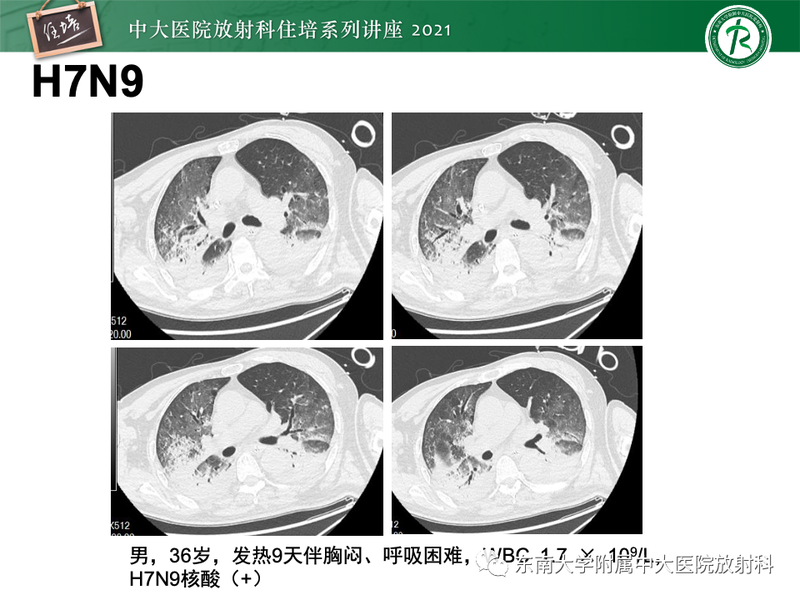

常见细菌性肺炎、病毒性肺炎影像诊断与鉴别